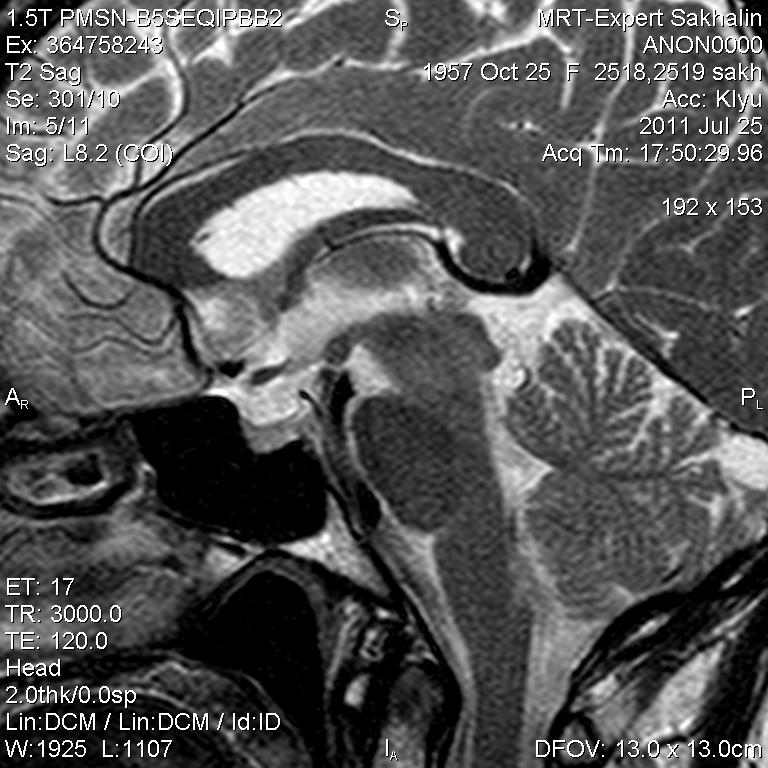

Женщина.6 лет назад выявлено образование левой доли нейрогипофиза.Пришла на контроль.

Постконтраст

Мне самой показался случай не совсем ясным, но динамик четко показывает участок с отставанием в контрастировании, воронка смещена вправо-о чем  думать бедному начинающему специалисту?